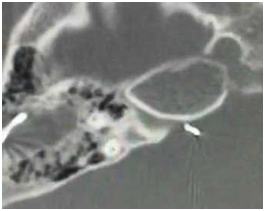

Case of the electrode placement into the IAC

There was no partition between basal turn of the malformed cochlea (incomplete partition type II) and IAC, electrode was placement through IAC into the cerebellopontine angle (Figure 4). The electrode was being removed, and simultaneous reimplantation of a same implant into the cochlea via an extended same cochleostomy. A postoperative CT scan of temporal bone demonstrated correct electrode placement in the right cochlea (Figure 5).

Figure 4 Axial CT of right temporal bone. Electrode was placement through IAC into the cerebellopontine angle.

Figure 5 A postoperative CT scan of temporal bone demonstrated correct electrode placement in the right cochlea.